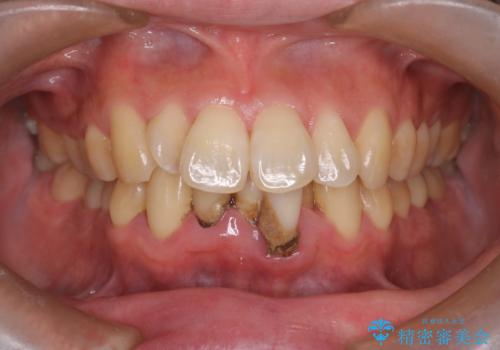

【インビザライン】前歯のガタガタを治したい

- 前歯のガタガタを主訴に来院されました。

上の歯の前突も気になってたため、奥歯の遠心移動も行いながらインビザラインにて治療を行いました。

今回は奥歯の遠心移動とIPRを行って配列しています。